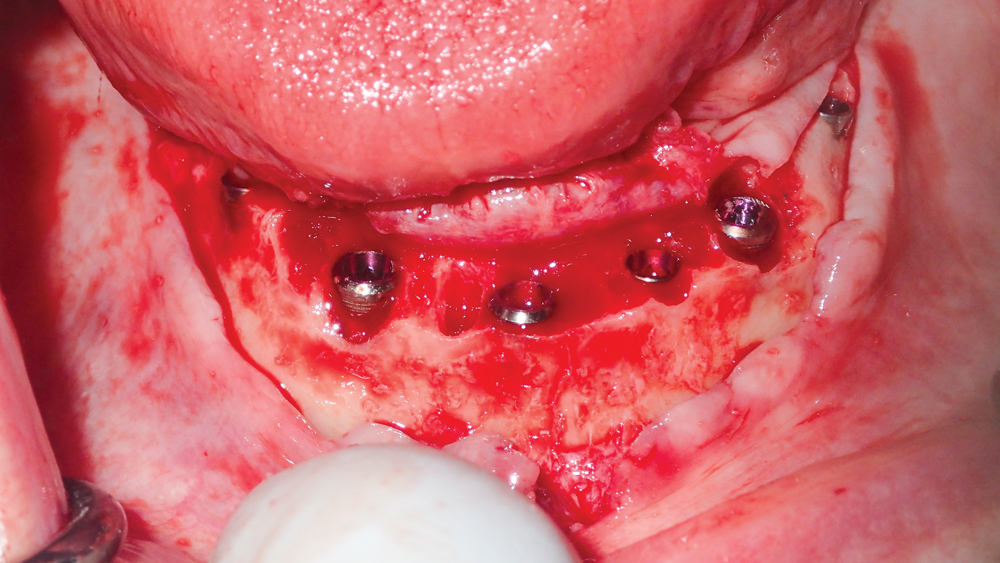

This patient was unhappy with the esthetics of her existing upper denture as well as the discomfort and instability caused by her loose-fitting mandibular partial denture. Although her concerns with the maxillary denture could be addressed with a new, more esthetic appliance, she preferred implant treatment for her mandible, where a fixed solution was needed to adequately restore function, stability and comfort.

The patient’s remaining mandibular teeth were extracted followed by immediate implant placement and delivery of a fixed provisional appliance. After integration of the implants, the prosthetic designs for the new upper denture and lower implant restoration were determined in tandem. Ultimately, the dual-arch restorations addressed the functional and esthetic challenges of the case while staying within the financial means of the patient, demonstrating the benefits of a flexible, multifaceted approach to restorative dentistry.

The dual-arch restorations addressed the functional and esthetic challenges of the case while staying within the financial means of the patient.